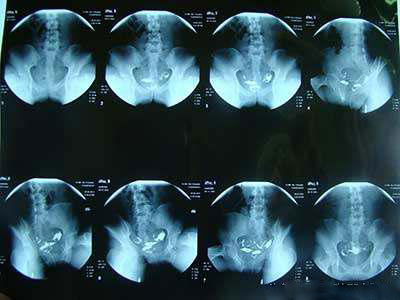

输卵管造影

输卵管造影是提供宫颈管、官腔大小、形状和子宫轮廓情况,可明确输卵管是否通畅,并在程度上反映输卵管的形态和功能,广泛用于妇科临床,一直被认为是输卵管功能检测的首选方法。

它的优点是简便、迅速、诊断较明确,可提供输卵管内部结构信息,判断输卵管是否通畅,明确输卵管阻塞部位,较为直观的显示输卵管的柔顺度以及子宫内膜的某些病变,具有潜在的治疗作用。

很多患者担心输卵管造影检查会不会损伤子宫,这个担心是不必要的。造影剂注入宫腔时,冲刷作用可能会损伤一点子宫内膜,但我们也知道子宫内膜每个月都会自行脱落形成月经,所以这一点儿损伤对人体是没有任何影响的。